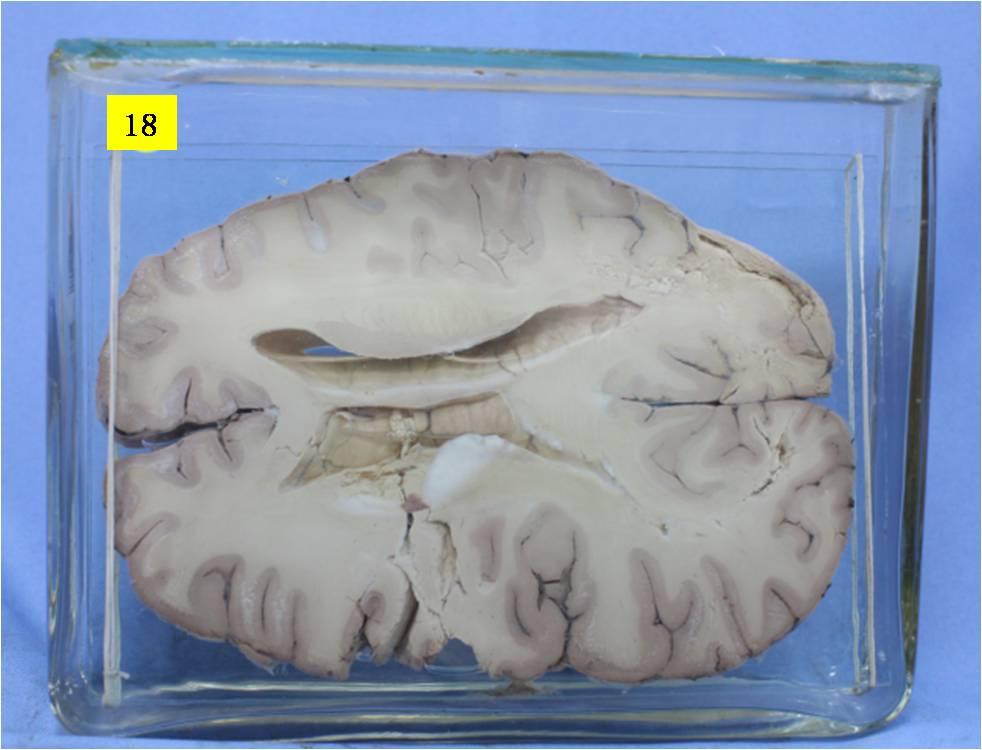

神经疾病-59-18. 大脑半球多发贫血性梗死

大脑半球水平切面双侧不对称,左侧大脑半球肿大,侧脑室透明隔右移,左侧基底节尾状核及相邻大脑白灰质液化坏死,部分脱落,右侧侧脑室后脚附近及双侧枕叶白质可见灶性液化性坏死。